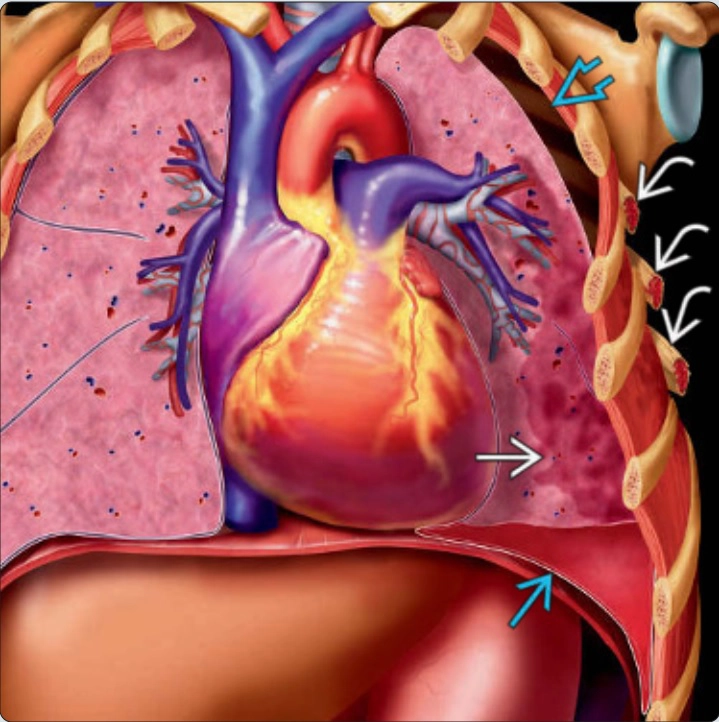

Giải phẫu trung thất

16/03/2026